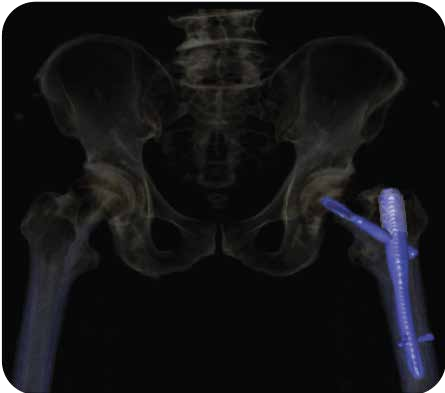

Incisive CT的O-MAR技术能消除金属伪影,能清晰显示移植物的位置及临近组织结构。

▲ 骨折术后、内固定器材清晰显示